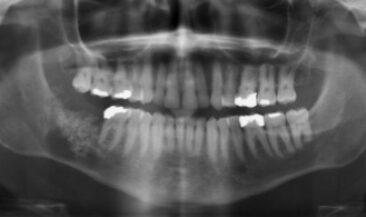

Wisdom tooth removal with enucleation of dentigerous cyst and bone graft